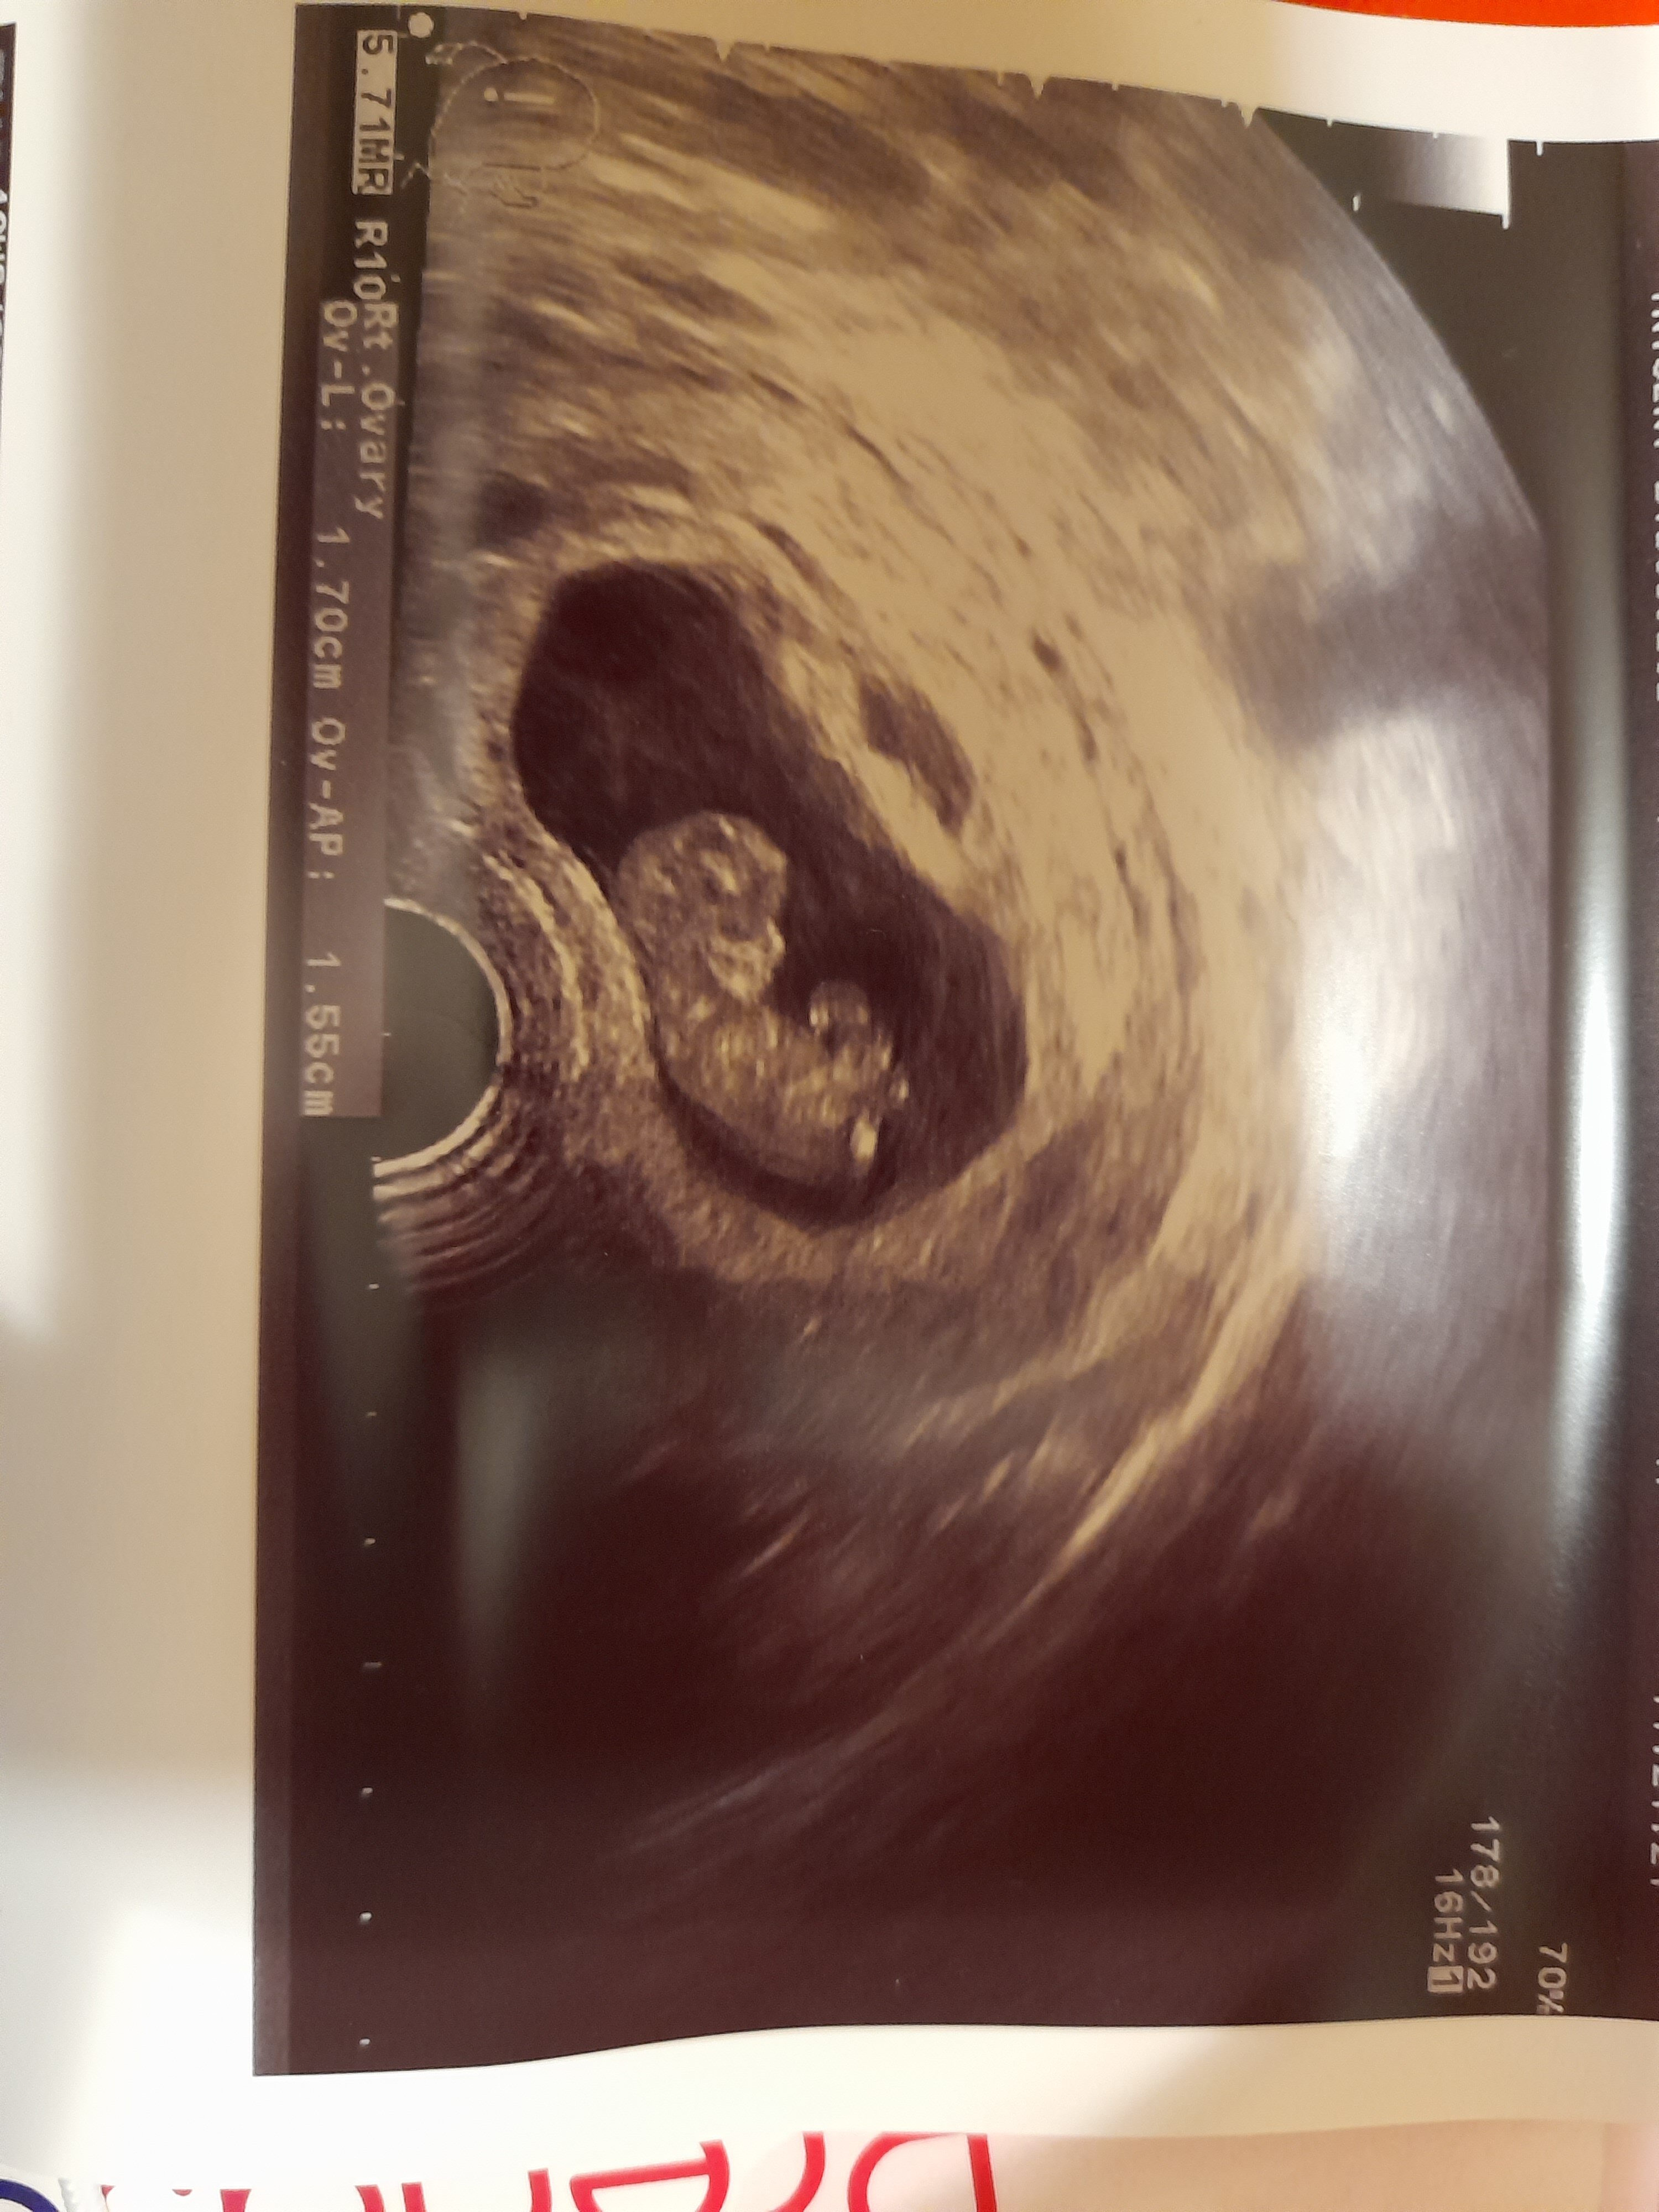

Po wizycie. 10+2 z usg. Crl 34mm. Akurat podskoczył jak gin robil usg, wiec już widziałam jak sie rusza. Serce bije. Na razie wszystko ok.

Załączniki

• 20211201_184556.jpg

20211201_184556.jpg

1 MB · Wyświetleń: 113